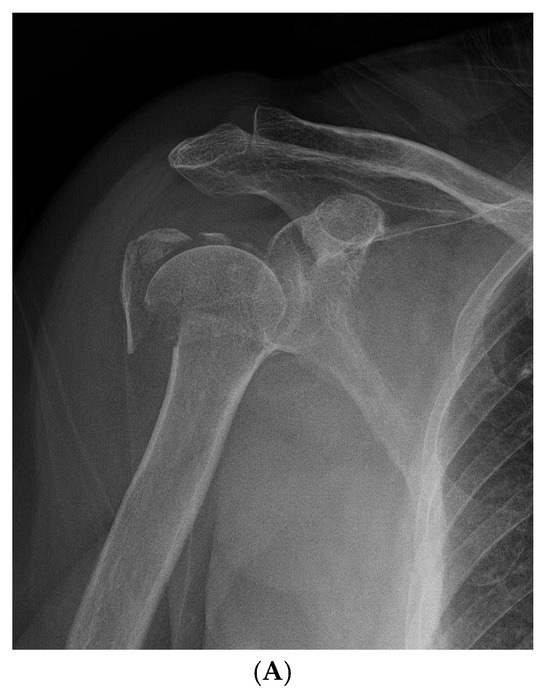

Figure 3.

Representative Case 2: 58-year-old male with Neer type-4 valgus impacted proximal humeral fracture treated with ORIF and conventional rehabilitation. (A) Preoperative AP radiograph showing severely displaced valgus impacted fracture. (B) Preoperative axial CT scan illustrating fragment displacement and rotation. (C) Immediate postoperative AP radiograph showing satisfactory reduction and internal fixation. (D) 24-month follow-up AP radiograph demonstrating complete fracture healing, and maintained functional range of motion.